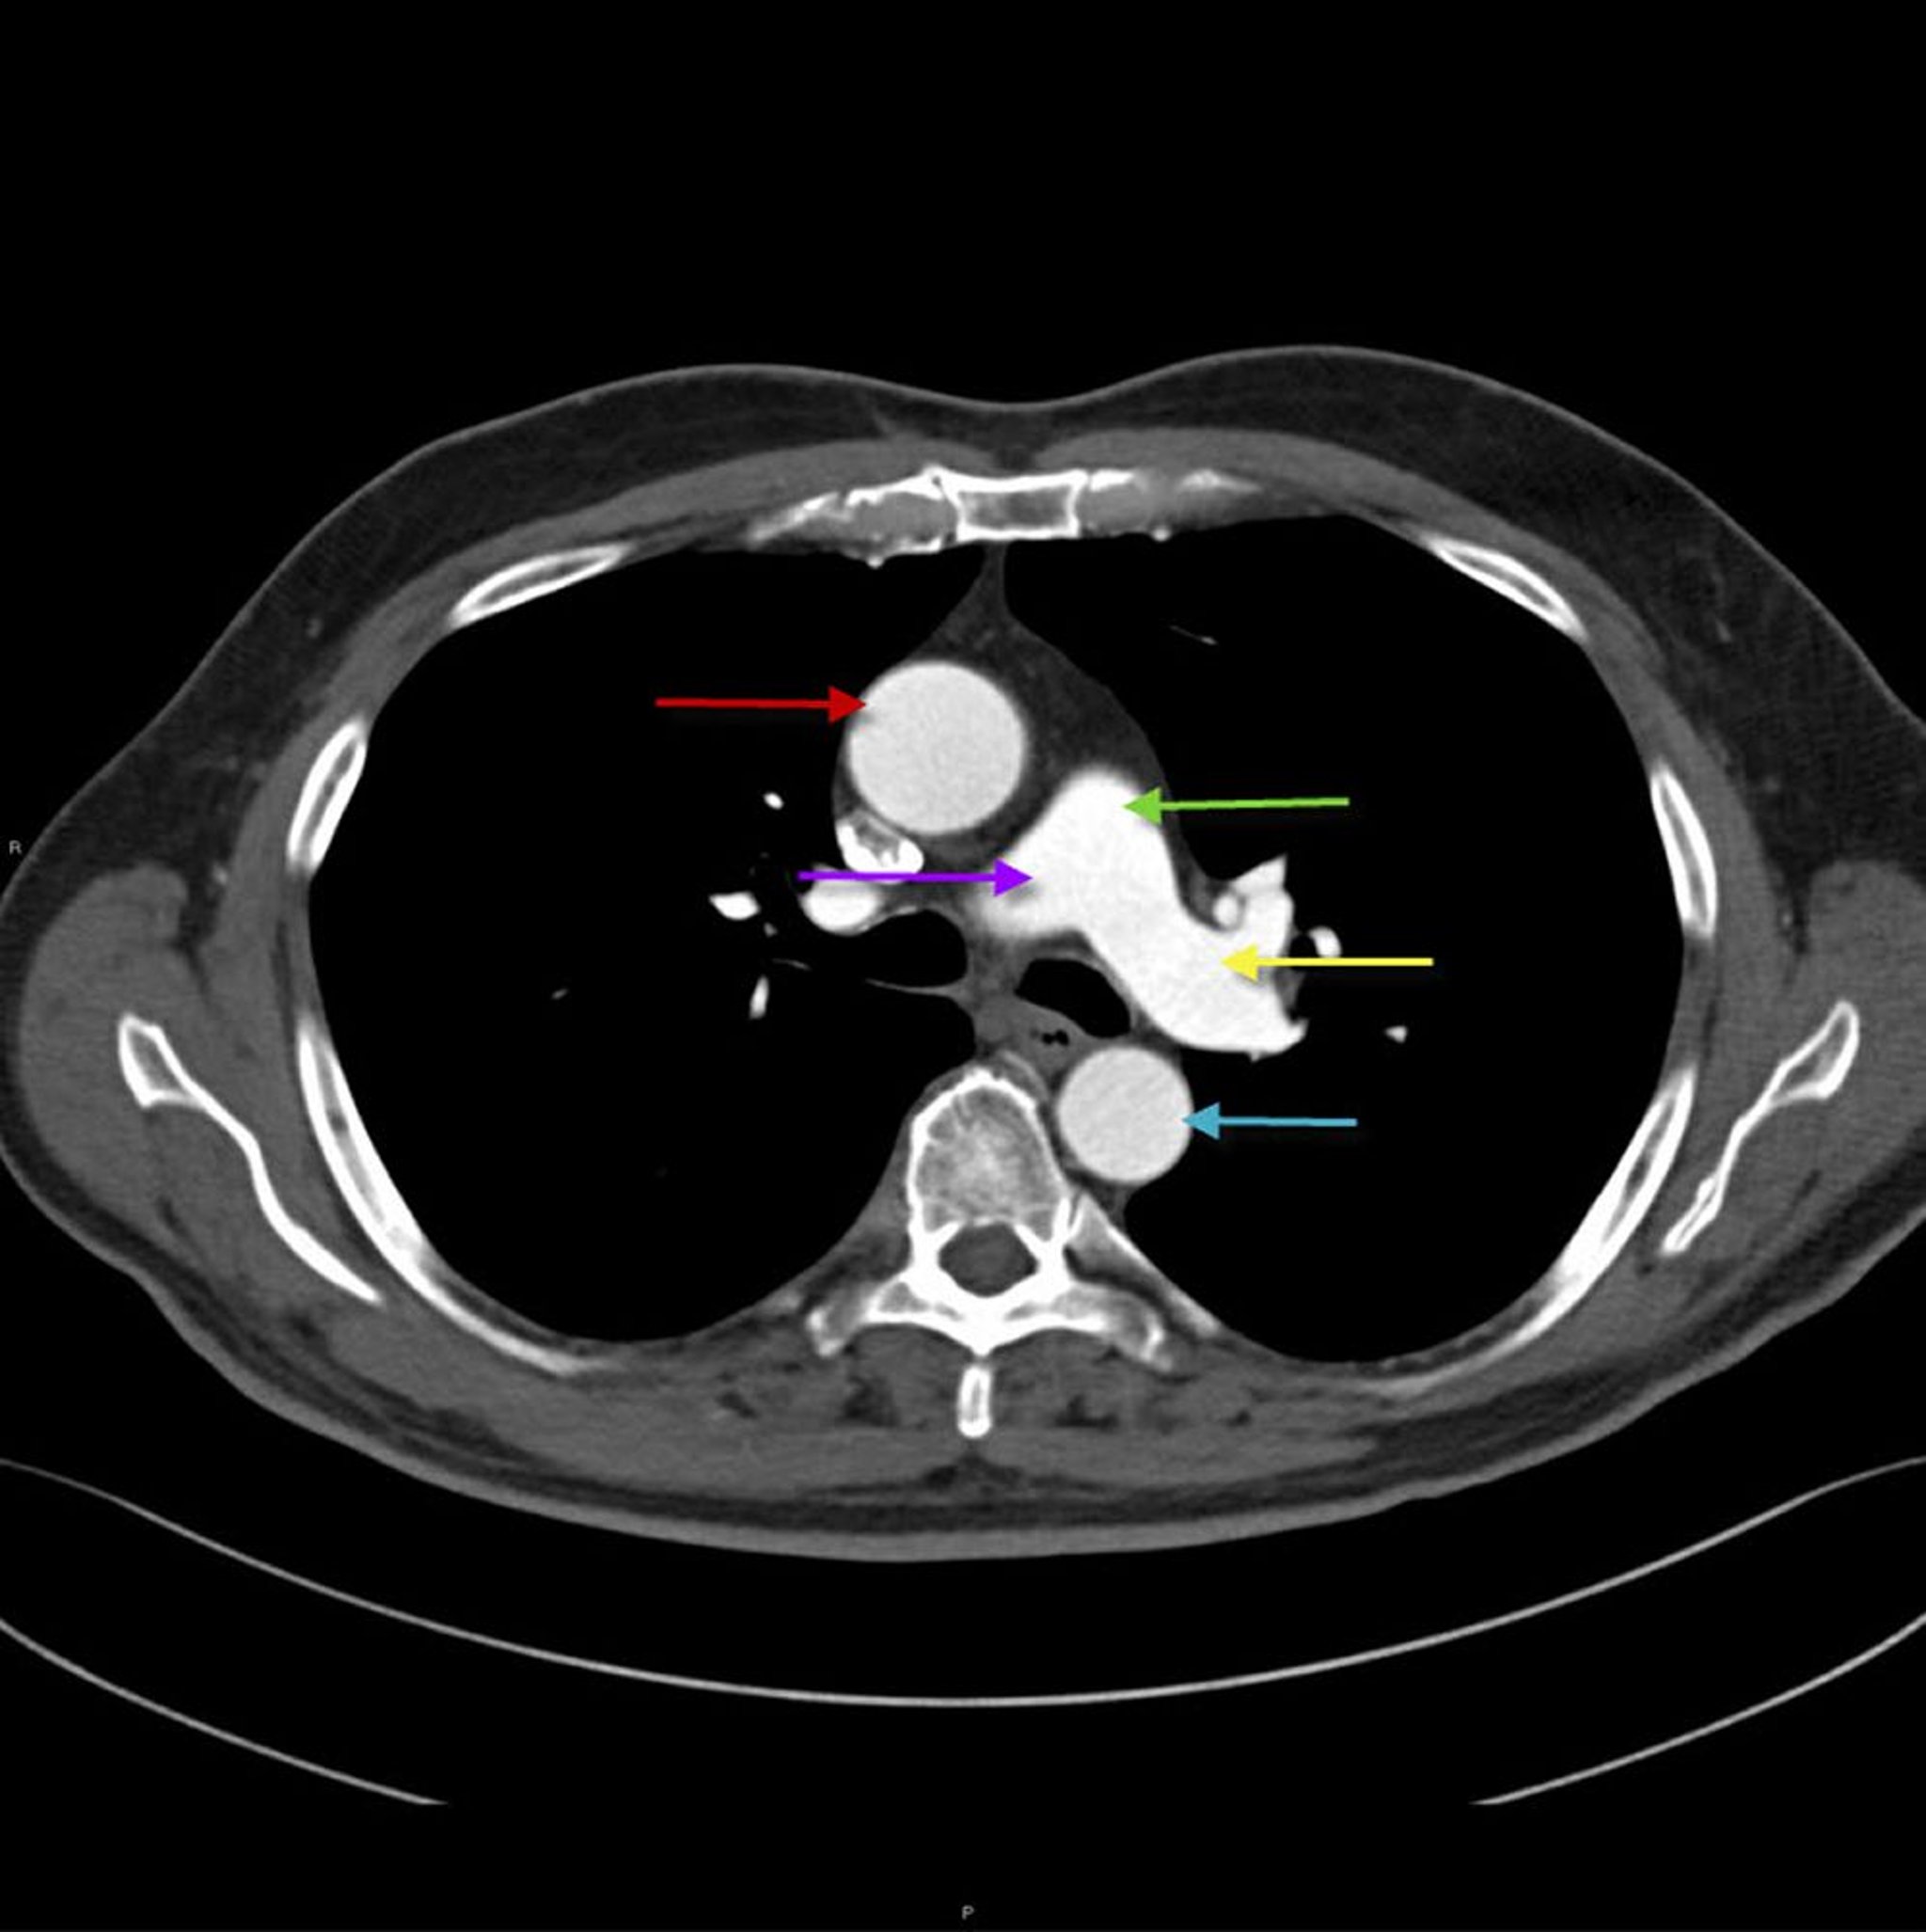

TC torácica que muestra la anatomía de la aorta y la arteria pulmonar

Esta imagen muestra la aorta torácica ascendente (flecha roja) con la aorta torácica descendente (flecha azul). La arteria pulmonar principal (flecha verde) se divide en la arteria pulmonar derecha (flecha púrpura) e izquierda (flecha amarilla).